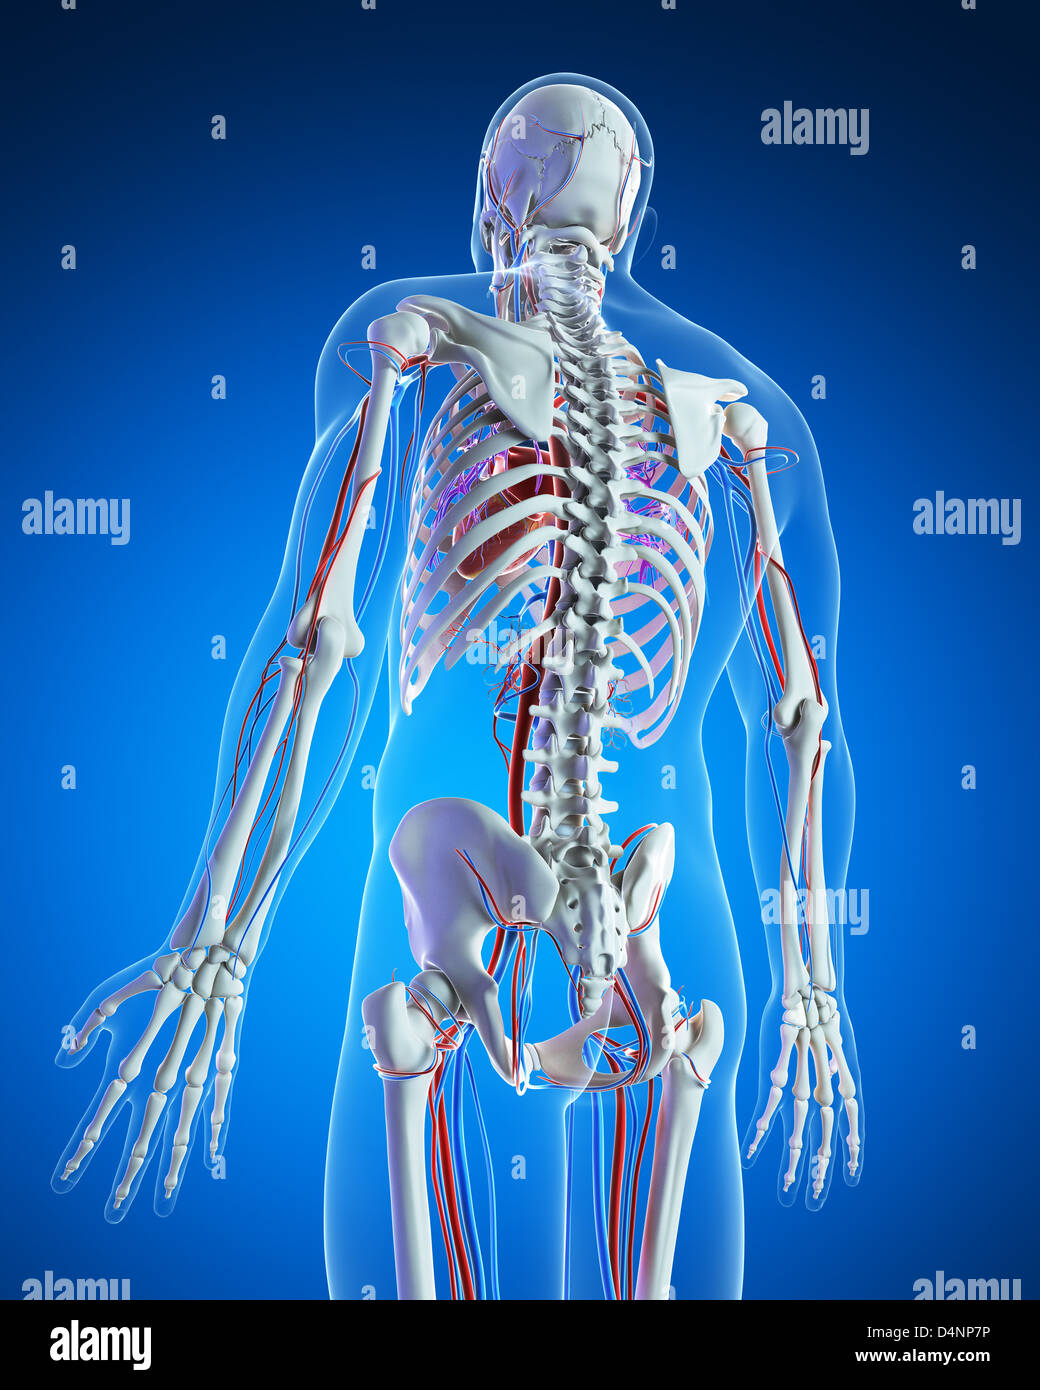

Vascular system Stock Photohttps://www.alamy.com/image-license-details/?v=1https://www.alamy.com/stock-photo-vascular-system-54568462.html

Vascular system Stock Photohttps://www.alamy.com/image-license-details/?v=1https://www.alamy.com/stock-photo-vascular-system-54568462.htmlRFD4NPHJ–Vascular system

Vascular system Stock Photohttps://www.alamy.com/image-license-details/?v=1https://www.alamy.com/stock-photo-vascular-system-54568186.html

Vascular system Stock Photohttps://www.alamy.com/image-license-details/?v=1https://www.alamy.com/stock-photo-vascular-system-54568186.htmlRFD4NP7P–Vascular system

Vascular system Stock Photohttps://www.alamy.com/image-license-details/?v=1https://www.alamy.com/stock-photo-vascular-system-54546602.html

Vascular system Stock Photohttps://www.alamy.com/image-license-details/?v=1https://www.alamy.com/stock-photo-vascular-system-54546602.htmlRFD4MPMX–Vascular system